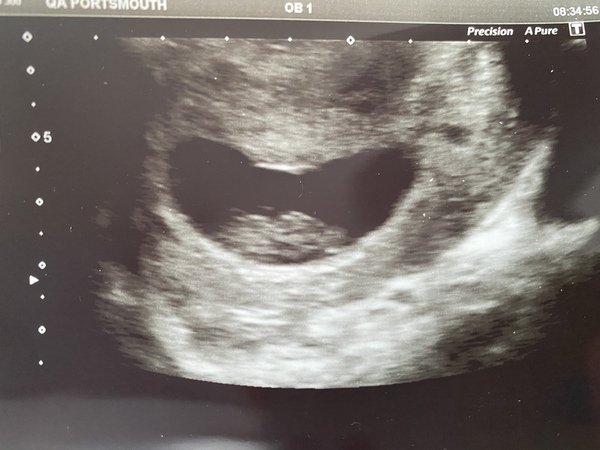

Went for an early scan today at what I thought was 7+5 but they have now measured me 8+3. Saw a heartbeat and it was all perfect 🥰 EDD now 13th August ☺️